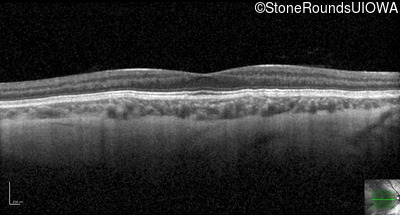

Optical Coherence Tomography - Left - 20/100

Exemplar / OCT Stack